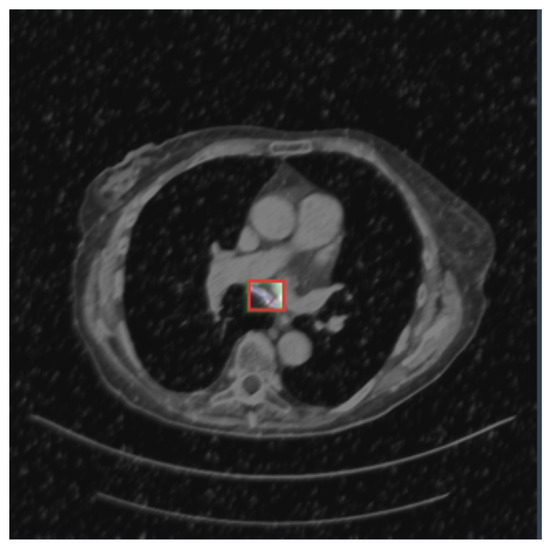

- Adenocarcinoma (Blue Line):

- -

- The blue line represents the precision–recall relationship for the adenocarcinoma class.

- With an average precision (AP) of 0.734, the model performs relatively well in detecting adenocarcinoma, maintaining high precision and recall values.

- Cancer (Orange Line):

- The orange line represents the performance for the cancer class.

- An AP of 0.588 indicates moderate performance, with a noticeable drop in precision as recall increases, suggesting that the model struggles more with this class compared to adenocarcinoma and nodules.

- Nodule (Green Line):

- The green line shows the precision–recall for nodules.

- With the highest AP of 0.802, the model performs best on this class, indicating high precision and recall across most thresholds.

- All Classes (Bold Blue Line):

- The bold blue line represents the overall performance across all classes, with an mAP@0.5 of 0.708.

- The mean average precision (mAP) at an IoU threshold of 0.5 provides a single metric summarizing the model’s performance across all classes.

- An mAP@0.5 of 0.708 suggests that the model has a strong overall detection capability, balancing precision and recall well.